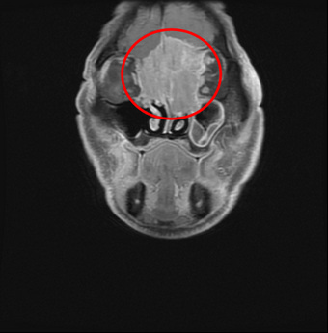

右圖:黃先生罹患罕見的「嗅神經母細胞癌」,且腫瘤已長到6公分,從大腦額葉到雙側眼框到鼻腔上部,佔據整個前顱底並侵蝕到鼻樑骨。

周昱甫副主任表示,第一次看到黃先生時,便發現他眉間額頭微凸、眼距較寬,經過電腦斷層掃描、病理切片檢查,確診腫瘤為罕見的「嗅神經母細胞癌」,且腫瘤已長到6公分,從大腦額葉到雙側眼框到鼻腔上部,佔據整個前顱底並侵蝕到鼻樑骨,雖病人視力未受到影響,但是橫向生長的腫瘤因壓迫到眼外肌,導致病人眼睛無法聚焦,與典型的嗅神經母細胞癌的常見症狀鼻塞、流鼻血等表現症狀大不同。